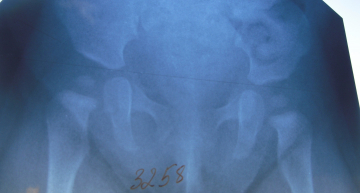

Здравствуйте! Беспокою Вас с г.Борисова. У меня сын 6,5 мес. На плановом осмотре у ортопеда в 6 мес. выявлены ассиметричность ягодичных складок ( слева смещены на 0,7 см вверх) и ограниченность отвода левой ножки до 70 градусов. Отправили нас на ренген. По ренгену: точки окостенения головок бедренных костей равновеликие, крыши вертлужных впадин не скошены (АУ 22 градуса справа и 19 градусов слева), без деформаций, линии Шенгона прерываются с обеих сторон. Заключение: предвывих т/б суставов справа и слева.Рекомендовано широкое пеленание и гимнасика. Ребенок имеет генетическую предрасположенность к данному заболеванию, т.к у меня в детстве был диагноз врожденный вывих бедер. Оперирована, сейчас в возврасте 26 лет стою на учете у ортопеда с диагнозом коксартроз 3 степени слева и 2 степени справа.